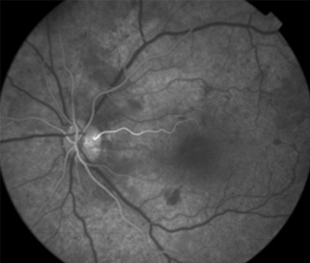

Angiografía OD

Angiografía OI

- Angiografía: teñido arterial, escape capilar, más tardíamente, no perfusion arteriolar y venular con teñido de las paredes vasculares y dilatación venosa.